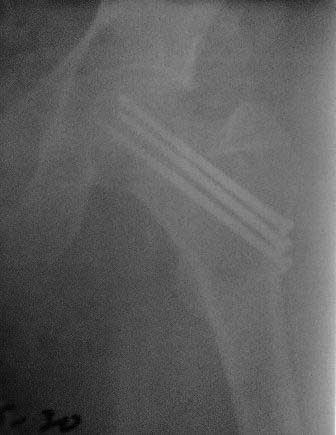

> Обратился б-ной около 40 лет, три месяца назад

>    P.S.   Р-снимки сразу после операции,  и вчерашные.

Какой из них сразу после и какой вчерашний? И можно ли их вообще сравнивать

друг с другом?..